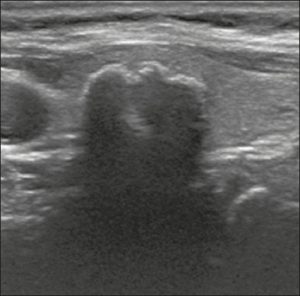

Hình 21. Hình ảnh nhân giáp dạng đặc (2 điểm), giảm âm (2 điểm), cao hơn rộng (3 điểm), có đường bờ không xác định (0 điểm), và không có các ổ tăng âm hay bóng lưng (0 điểm). Do đó, tổng điểm là 7 điểm và mức độ nguy cơ được phân loại là TR5.